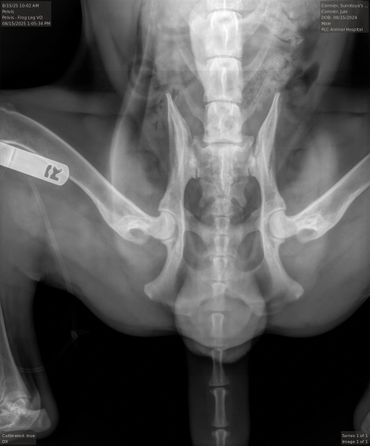

Hips (SV): Normal

HD Breeding Value (SV): 83

PennHIP: L: 0.4, R: 0.42